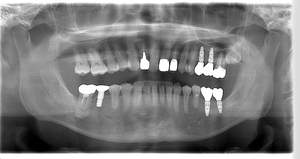

レントゲン写真

- 透過像

| 年齢 | 50代・男性 |

|---|---|

| 主訴 | 右下歯が疼く |

| 治療内容 | ・右下6番インプラント ※1:FGG(遊離歯肉移植術)とは、足りない歯ぐきを上顎から上皮を切り取り移植する外科手術 |

| 治療費 | 合計:902,000円(税込) ■内訳 |

| 治療期間 | 9ヵ月 |

| 治療方針 | 右下の当該歯は歯根破折により保存不可能と診断しました。歯周疾患も伴っていたため抜歯後に骨吸収※1が大きく起こることが予測できました。チタンメッシュ併用骨再生誘導法(GBR※2)を選択しインプラント埋入と同時に行い自然な歯槽骨のラインを再現しました。またGBRを行う際にインプラント辺縁の付着歯肉の減少が起こる為、遊離歯肉移植術(FGG※3)を行い清掃性を考慮した形態に仕上げました。 ■治療方針の解説 治療した右下の歯をレントゲンで撮影したところ根本の部分に黒く写る箇所があり「根尖性慢性周囲炎※1」と診断。また歯周病も進行していました。 ※1 骨吸収・・・歯槽骨という歯を支える骨がなくなっていくこと |

| 担当者所見 | 主訴の右下だけでなく歯茎の腫れ、発赤があり不良補綴や不良充填など他にも治療箇所が多数ありました。プラークコントロールが不良であった為まずはブラッシング指導を行いセルフケアの重要性を理解していただくところからスタートしました。 右下6番の歯はインプラント治療を行なった結果審美的にも機能的にも患者様の満足を得ることができました。骨造成と歯肉移植も行なった為インプラントを支える十分な歯周組織の獲得ができたと思っております。 |